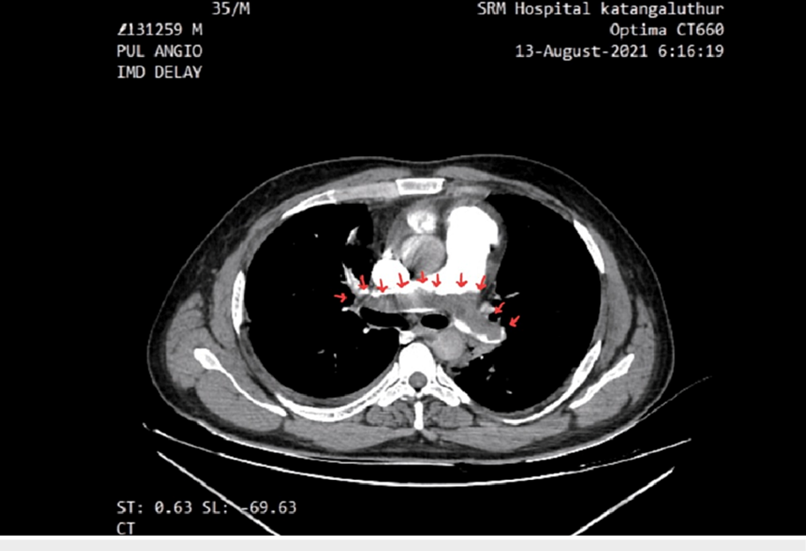

Nhóm thuyên tắc phổi: trong tình trạng này, cục máu đông thường xuất phát từ hệ tĩnh mạch sâu (như tĩnh mạch chi dưới), sau đó di chuyển lên phổi và làm tắc một phần hoặc toàn bộ động mạch phổi. Mức độ biểu hiện lâm sàng phụ thuộc vào kích thước và vị trí của huyết khối. Bệnh nhân thường xuất hiện khó thở đột ngột, đau ngực kiểu màng phổi (tăng khi hít sâu), nhịp tim nhanh và có thể ho ra máu nếu có tổn thương nhu mô phổi [4]. Trong các trường hợp nặng, có thể xảy ra tụt huyết áp, suy tuần hoàn và nguy cơ tử vong cao nếu không được xử trí kịp thời.

![Rối loạn thông khí – tưới máu (V/Q): Phân tích cơ chế shunt, khoảng chết và các bệnh lý liên quan Hình CT cho thấy vùng khuyết thuốc trong động mạch phổi (mũi tên đỏ), biểu hiện của cục máu đông. Điều này làm cản trở dòng máu đến phổi → điển hình cho thuyên tắc phổi.

Nguồn: Abdo, Y. (n.d.). Computed tomography pulmonary embolism (CTPE) showing pulmonary artery embolus [Figure]. Researchgate](https://ykhoa.org/wp-content/uploads/2026/04/image-7.png)